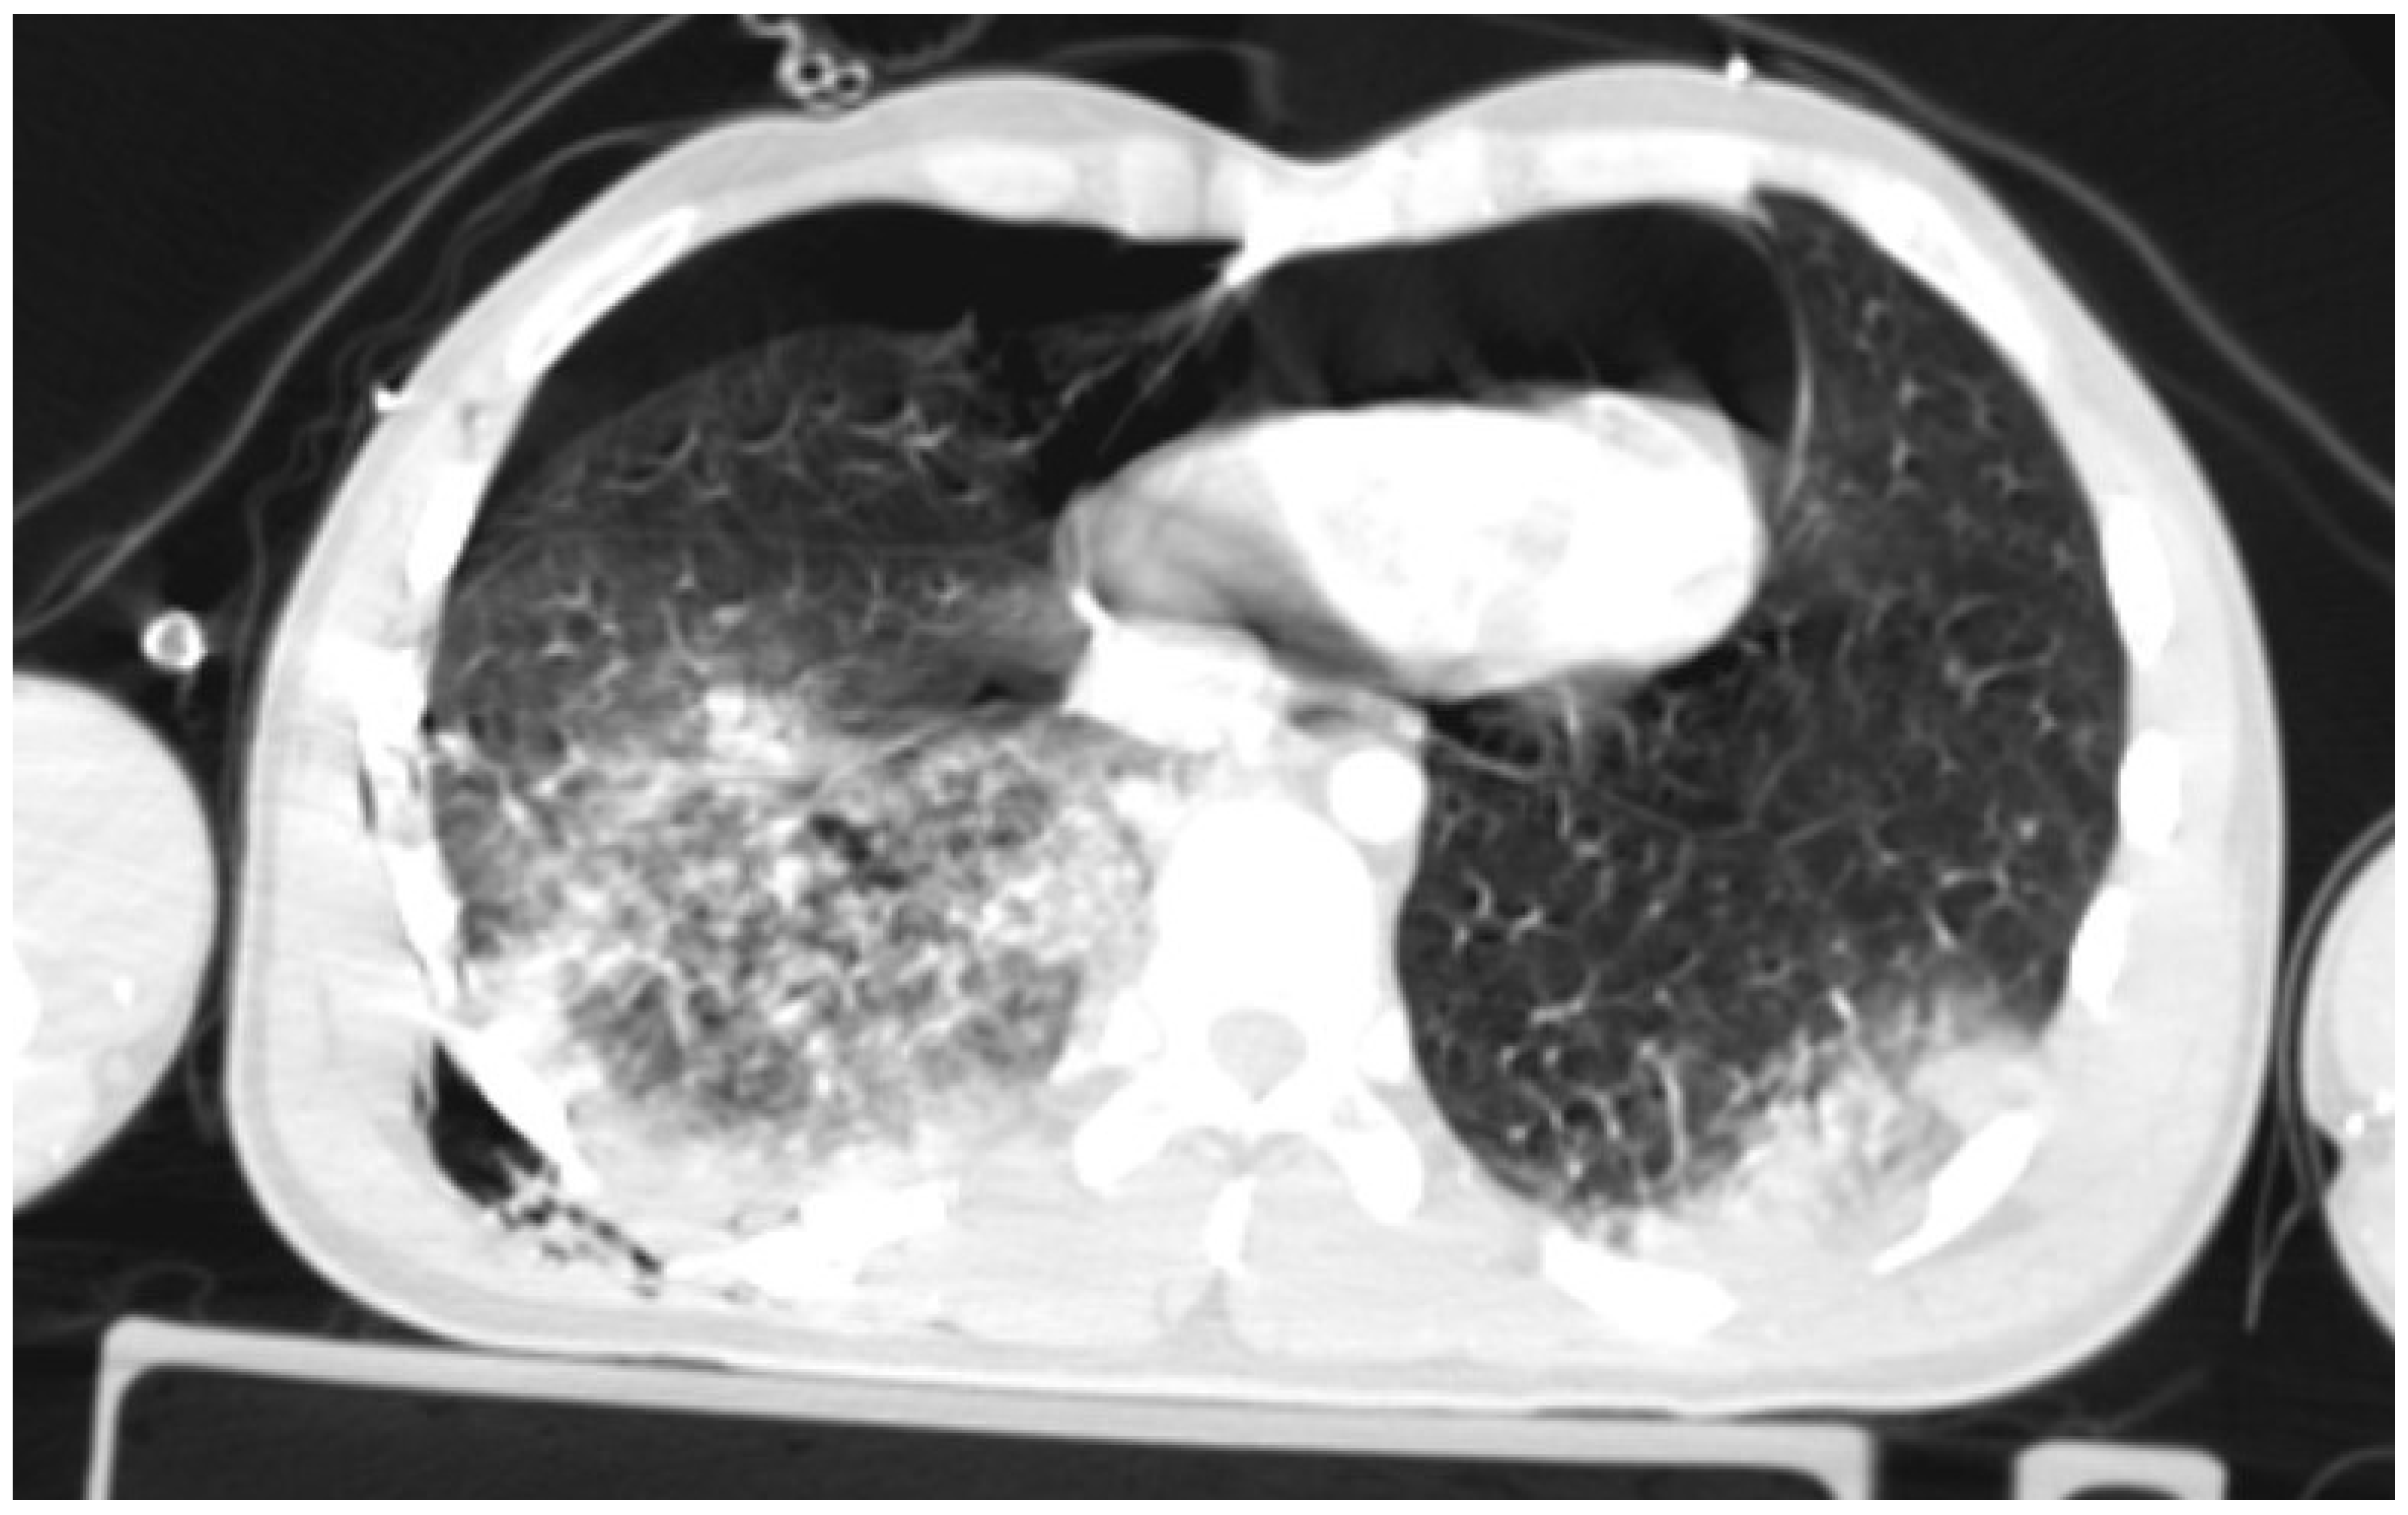

A CT (Computed Tomography) scan showed right-sided pneumothorax with a chest drain (the maximum width of pneumothorax 20 mm) and a pneumopericardium (max. 30 mm) with the symptoms of compression of the anterior wall of the heart. There were features of cardiac tamponade (Figure 1); there was a right lower lobe contusion and rib fractures from V to XII on the right side (some of the ribs fractured in multiple places with displacement); a right hemothorax up to 20 mm; a para cerebral hematoma in the left temporal region up to 3 mm; numerous sites of retroperitoneal bleeding along the iliac vessels (on the right side up to 30 mm in diameter), hematoma around the bladder and right iliopsoas muscle; a small hypodense area alongside to the right kidney up to 10 mm with a hypodense area adjacent to the liver up to 16 mm; a contusion of the soft tissues of the right buttock with hematoma (max. 30 mm); multiple fractures of the pelvis; a collapsed inferior vena cava; and an open fracture of the right elbow. The Injury Severity Score had a value of 50 points.

Figure 1. Pneumothorax and pneumopericardium with features of cardiac tamponade.